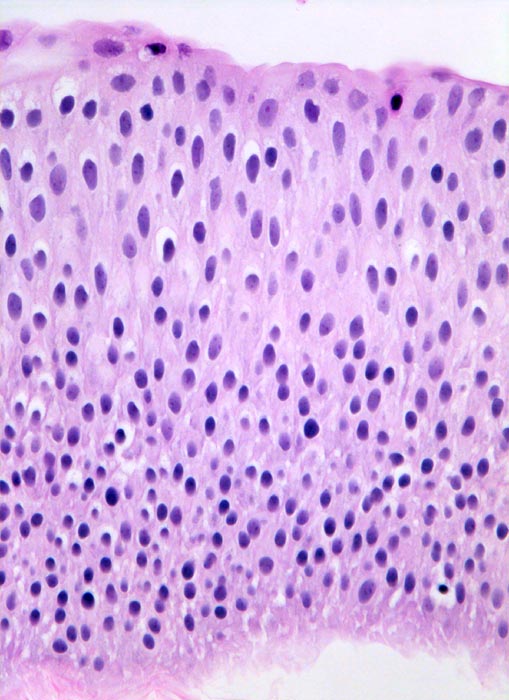

Das bedeckende Urothel des papillären Tumors ist deutlich verbreitert. Zellatypien sind nicht vorhanden (histologischer Grad 1).

Normales Urothel umfasst in der Regel weniger als 7 Zellagen.